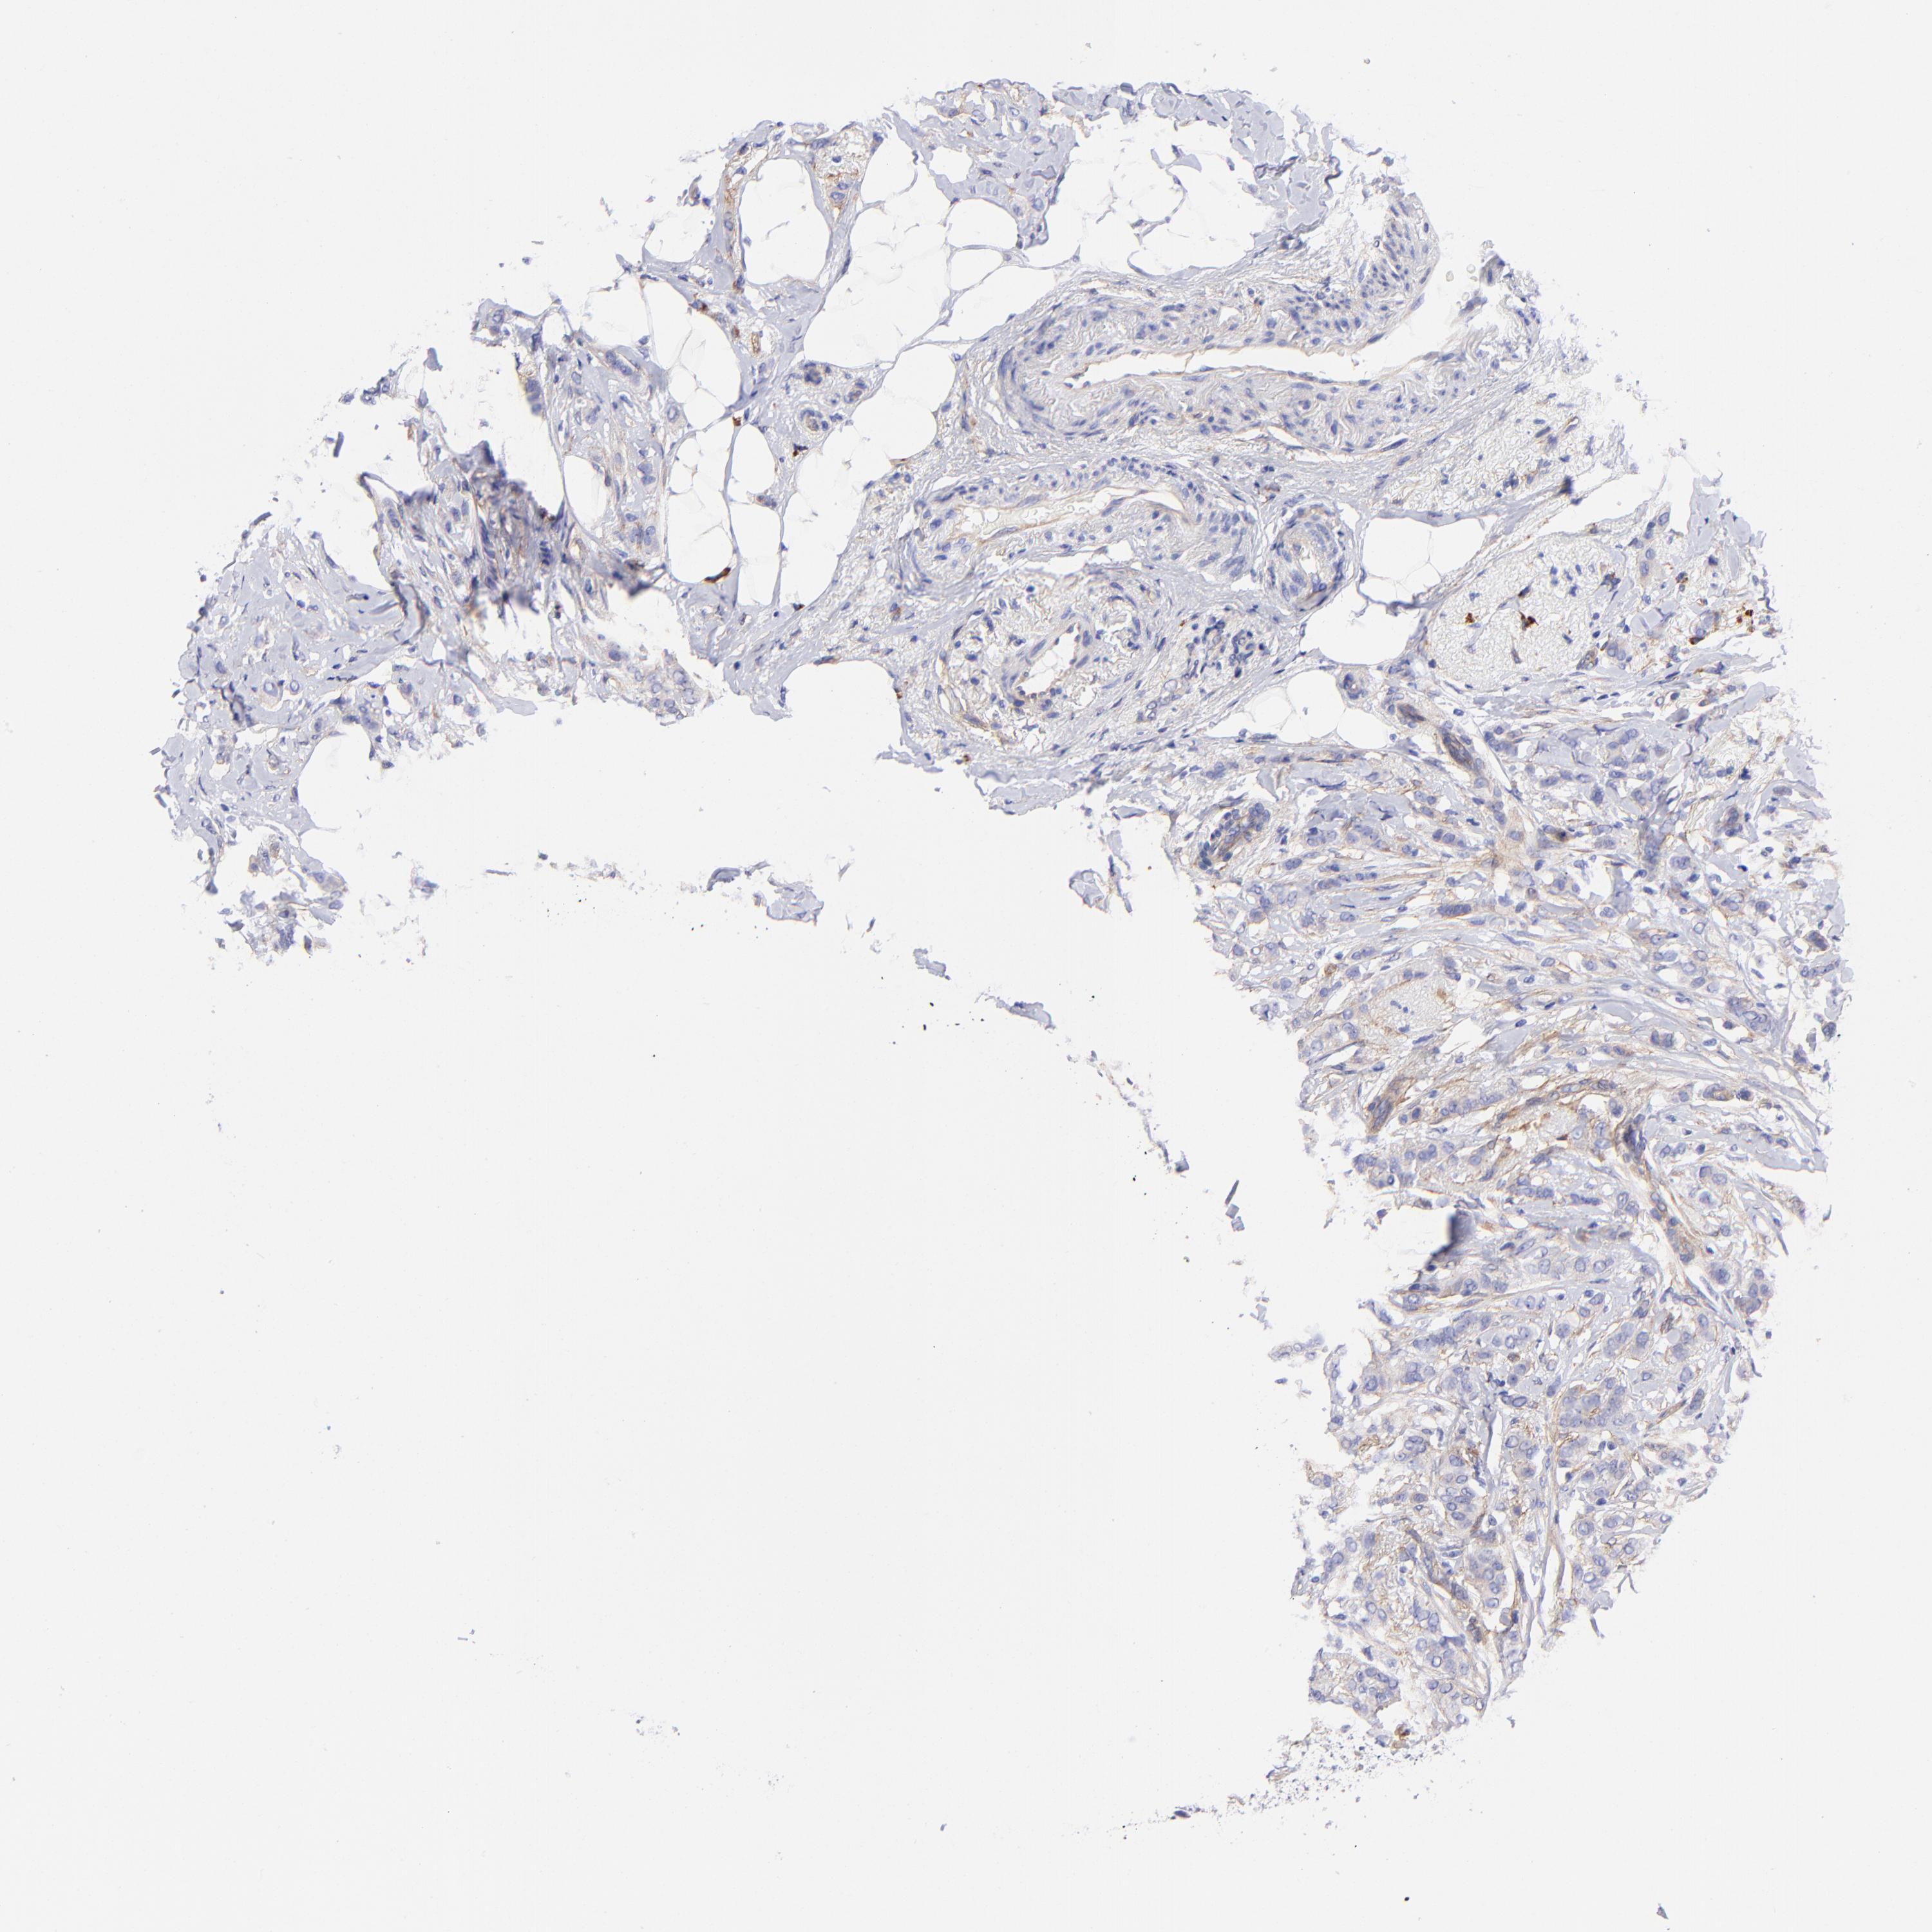

BRCA TCGA BRCA VALIDATION PROTEIN EXPRESSION

ANTIBODIES

AND

VALIDATION